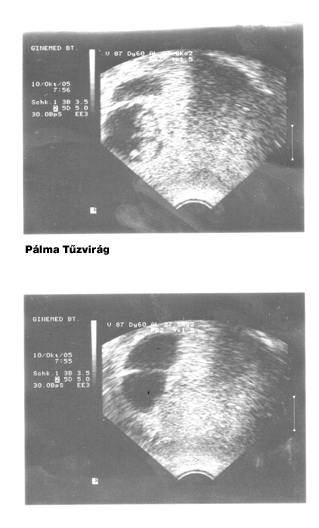

És íme a legelső UH-fotók:

Kép

úgy érzem, most végre elárulta magát: egyrészt 9-10 hetesen még LEHETETLEN megállapítani a magzat/ok (?) nemét, sőt még talán azt sem, hogy egy v. kétpetéjűek-e :shock:

másrészt, ha jól megnézitek a csatolt UH képeket, azokon 2005. okt. 10. dátum szerepel :roll:

bár igazából önmagát csapja be, ha notórius hazudozó, mindenesetre én jót derültem "Pálma Tűzvirág" és "Lara Napsugár"

sztárfotóin :)

nem tudom, járt-e valamelyikőtők a Péterfyben UH-n, de érdekelne , hogy közkórházban az UH készülék vajon miért azt nyomtatja a leletre fejlécként, hogy "Ginemed BT." ??

Azt pedig hogy kétpetéjűek már akár a 7. héten is lehet látni egy sima 3D-s UH-al is!!! Kedves szakember...

Nekünk 2004-ben a 7. héten mondták meg hogy kétpetéjű ikrek, most 2007-ben pedig a 10. héten. :D :D